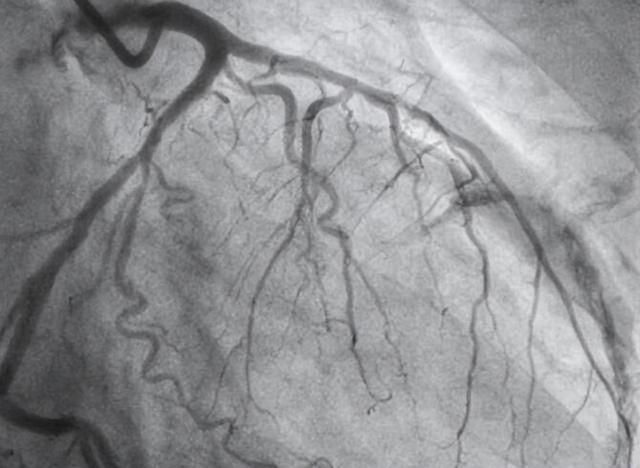

1.4 冠状动脉CT血管造影(CCTA)

CCTA 用于评估冠状动脉钙化进行冠心病危险分层,评估冠状动脉管腔和管壁结构,识别高危斑块与预后评价等。

CCTA的结果解读会采用的 Agatston 评分。Agatston 评分为 0,预示T2DM 患者10 年发生心血管事件的风险低;Agatston 评分 <100 提示心血管事件发生处于低风险(冠状动脉事件风险增加 2.1倍); 100~400 分提示心血管事件发生处于中风险(冠状动脉事件风险增加4.2倍);>400 分提示心血管事件发生处于高风险(冠状动脉事件风险增加 7.2倍)。

CCTA 的临床应用需要排除禁 忌证:如已知的严重碘对比剂过敏史、肾功能不全 [肾小球滤过率 <60 ml/(min·1.73 m2 )]、妊娠或怀疑受孕者等。

对于糖尿病病程较长(如10年以上)或可能存在无症状心肌缺血或合并大、中血管疾病的T2DM患者应完善CCTA检查,评估冠状动脉钙化、管腔狭窄程度和斑块负荷等。